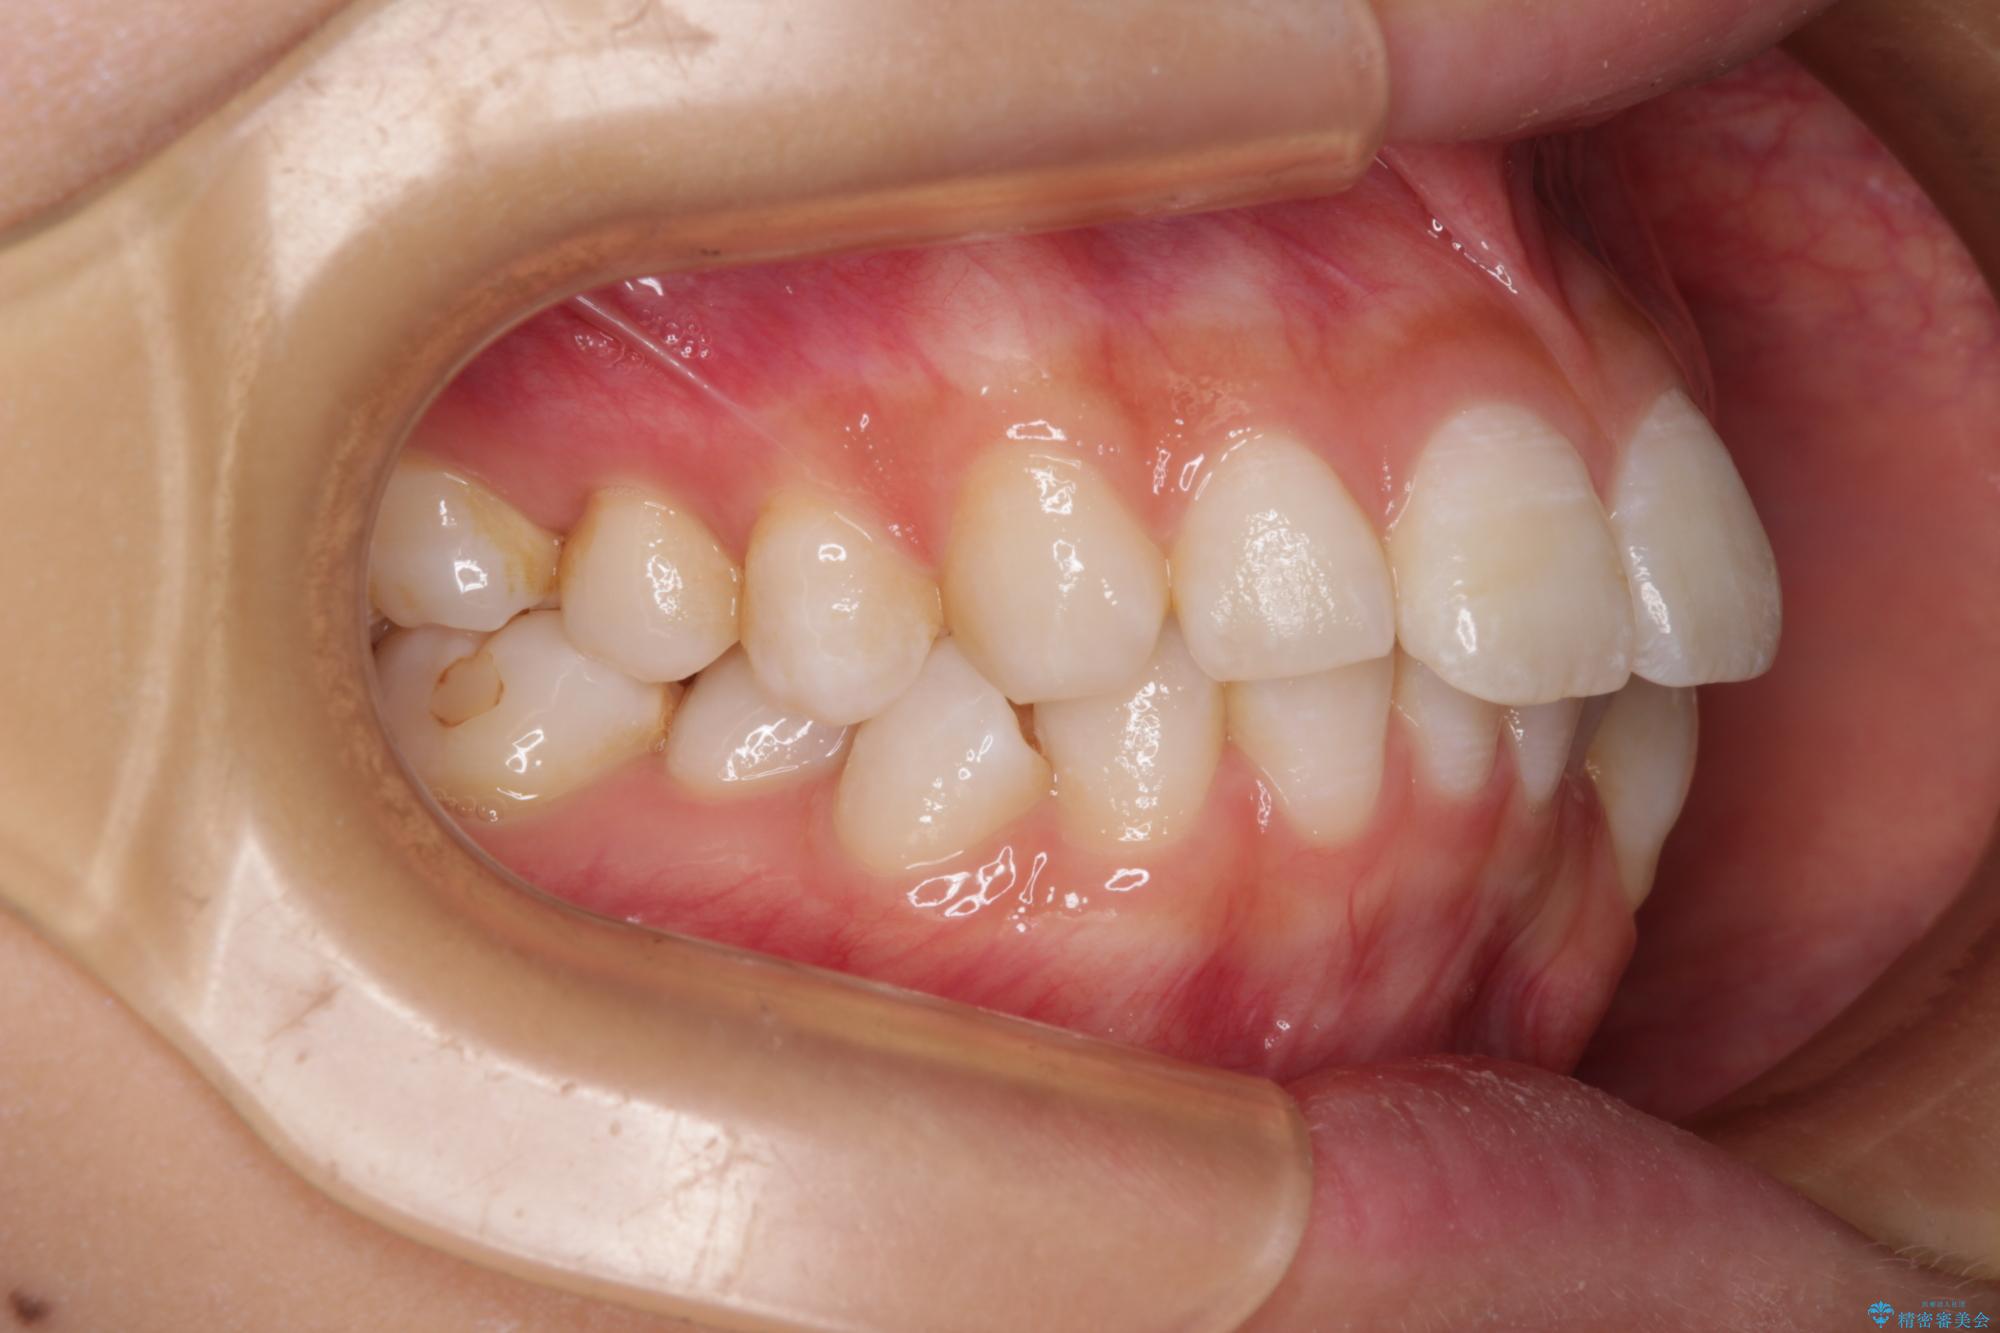

下唇に前歯が当たって跡が残ってしまう状態でしたが、スッキリとした口元に仕上げることができました。